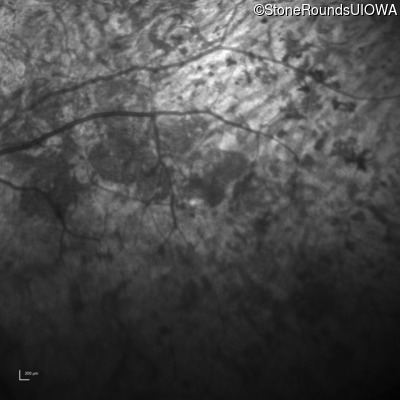

Infrared Fundus Photograph - Right - Light Perception

Exemplar